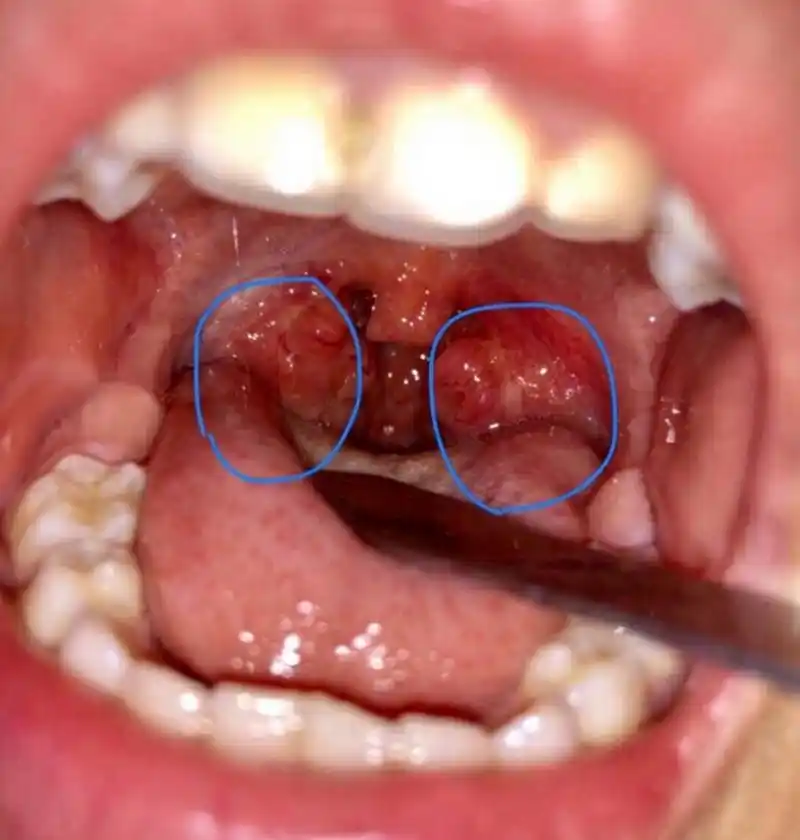

扁桃体炎